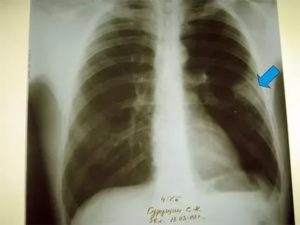

Основным признаком спаечного процесса на легком является наличие тени, которая появилась на снимке. Стоит учесть тот факт, что она никак не изменяет свою форму при вдохе и выдохе. Наряду с этим легочное поле будет менее прозрачным, а диафрагма и грудная клетка могут быть несколько деформированы. Зачастую спайки наблюдаются внизу легкого.

Для обнаружения легочных заболеваний в первую очередь используется флюорография. Эту процедуру необходимо проводить ежегодно, в основном она направлена на выявление ранней стадии туберкулеза. Однако опытный рентгенолог может выявить на снимке образовавшиеся плевральные спайки, которые выглядят тенями. Причем форма их не меняется в зависимости от вдоха и выдоха.

При необходимости дополнительно назначается рентген. Как правило, спайки располагаются в нижней части легкого. При этом будет более темная картинка, а также может быть частичная деформация грудной клетки и диафрагмы.

Основной атрибут, указывающий на спайку справа, является тень, видная на Rg-снимке. При этом затемнение не изменяется при вдохе и выдохе пациента. Одновременно снижается прозрачность легочной поверхности.

В тяжелых случаях наблюдается деформирование грудной клетки и диафрагмальной области. При таком состоянии диафрагма ограничивает свою подвижность. Чаще всего такие спайки расположены в нижних отделах легкого.

Распознать спайку по снимкам можно, если на нем легкие мутные, а еще при сравнении фотографий на вдохе и на выдохе. Спайка выглядит как тень, положение которой не меняется во время дыхания. Иногда наблюдается изменение формы и ограничение подвижности диафрагмы и грудной клетки.

Чаще всего спайки обнаруживают в нижней части легких.